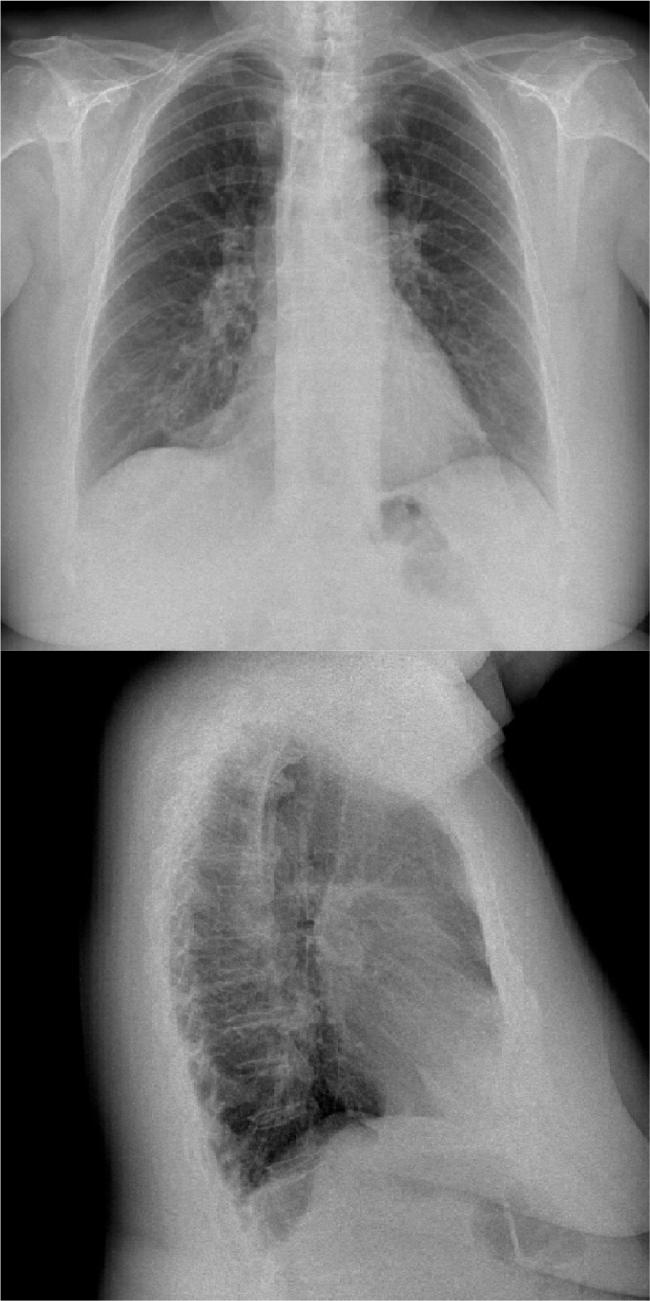

达沙替尼治疗超过5年后引发的乳糜胸:真的存在限度吗?

Dasatinib is a tyrosine kinase inhibitor used for treatment of some specific types of leukaemia. The development of pleural effusion is a known adverse effect of dasatinib and chylothorax is exceptional. No case has been reported beyond 5 years of treatment and extensive search for an alternative diagnosis is currently suggested in such scenario. The underlying mechanism is not currently clear. We describe a woman on dasatinib treatment for more than 10 years who developed chylothorax. Drug withdrawal resolved the chylous pleural effusion. We were able to find 14 additional cases of dasatinib-related chylothorax reported up until now.

达沙替尼是一种用于治疗某些特定类型白血病的酪氨酸激酶抑制剂。胸腔积液的发生是达沙替尼已知的不良反应,而乳糜胸则较为罕见。治疗超过5年的病例尚未见报道,目前在这种情况下建议广泛寻找其他诊断方法。其潜在机制目前尚不清楚。我们描述了一名接受达沙替尼治疗超过10年的女性,她出现了乳糜胸。停药后乳糜性胸腔积液得以缓解。截至目前,我们还能找到另外14例已报道的与达沙替尼相关的乳糜胸病例。